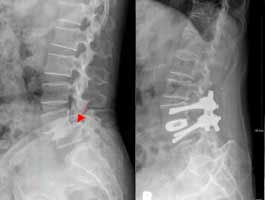

<ôÃßÀü¹æÀüÀ§Áõ>

<¼ö¼úÀü>

<¼ö¼úÈÄ>

¾çÃø

ÇÏÁö ¹æ»çÅëÀ» ÁÖ¼Ò·Î ¼ö¼ú ½ÃÇàÇÑ ¸ð½ÀÀ¸·Î

Ãß°æ ³ª»ç¸ø°íÁ¤¼ú ¹× Ãß°£À¶ÇÕ¼ú½ÃÇà·Ê